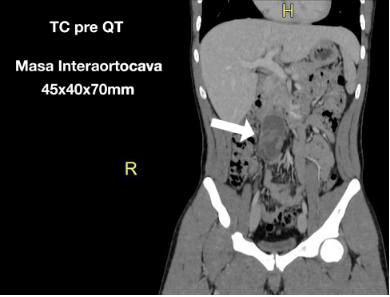

Imágenes radiológicas

Puede tratarse de imágenes o vídeos. Para facilitar su interpretación pueden remarcarse las áreas de interés como tumores, litiasis, estructuras vasculares mediante animaciones (flechas, círculos, etc.).

Para preservar la privacidad del paciente se tendrá que eliminar cualquier referencia que pueda desvelar su identidad.